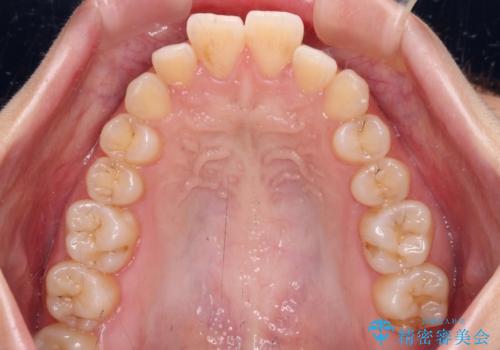

- 上下の前歯が突出しており、口が閉じにくいとのことで来院された患者様です。

上下前歯が著しく前突している状態であったので、上下左右の第1小臼歯4本を抜歯し、ワイヤー装置にて矯正治療を行うこととしました。

舌の突出癖があり、前歯の移動量も多くなるため、治療期間は長くなると予想されましたが、13ヶ月という予定の半分程度の期間で終えることができました。